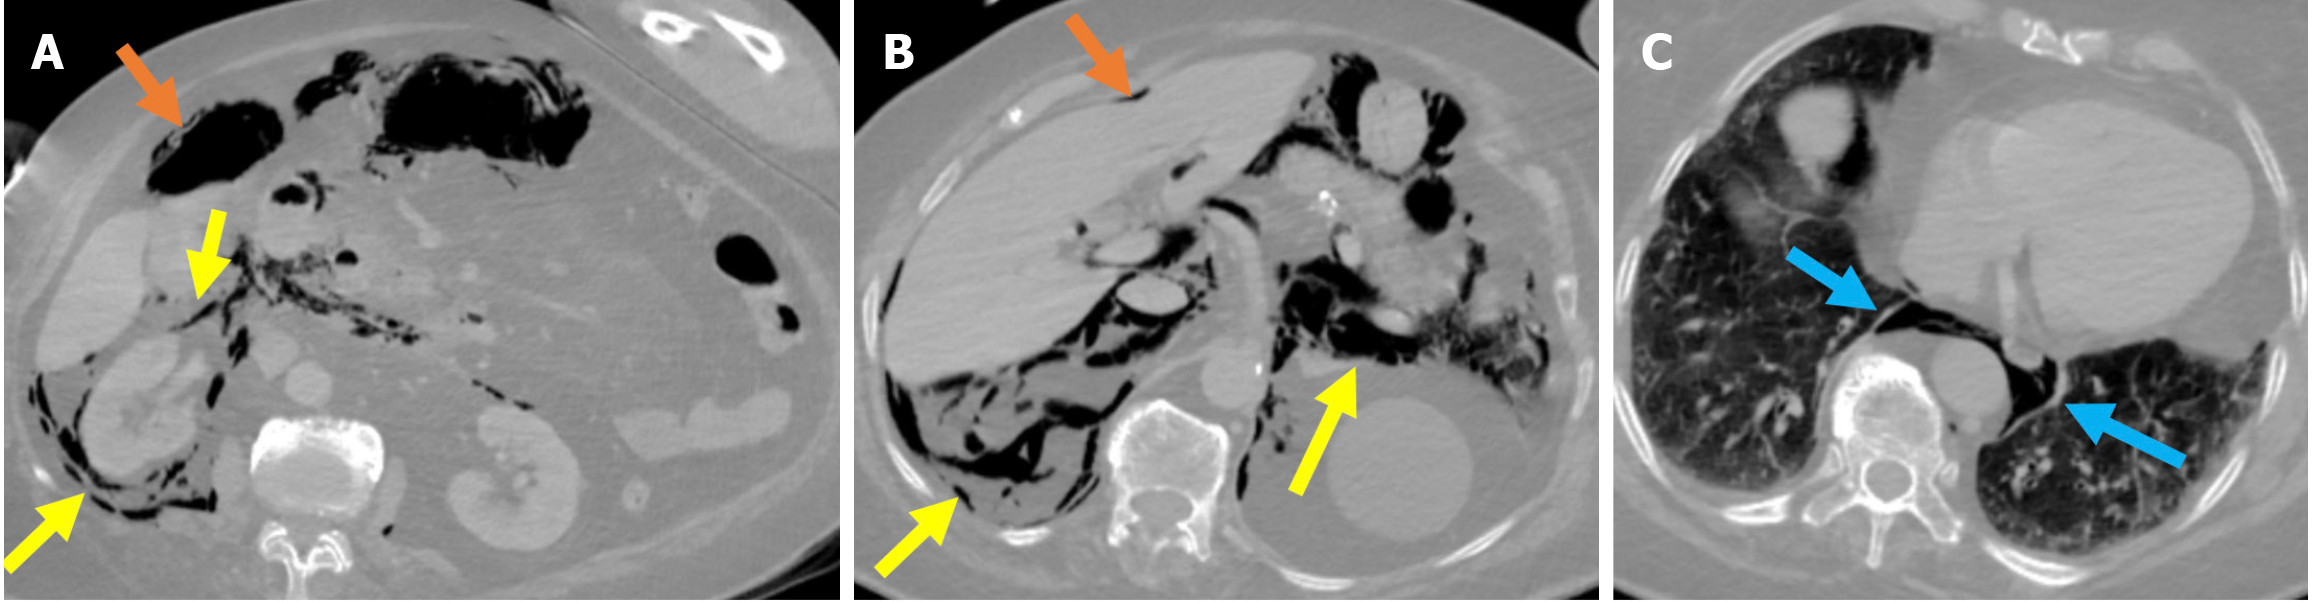

In the classification system proposed by Stapfer et al[17], perforations are categorized by decreasing severity and account for the need for surgical intervention, the mechanism of injury, and the anatomical location. Type I perforations involve full-thickness injuries of the duodenal wall caused by the endoscope (Figure 12). Type I perforations typically present during the procedure as sudden bleeding, collapse of the lumen, and difficulty maintaining insufflation[73]. Type II perforations are medial duodenal wall injuries related to sphincterotomy or papillotomy (Figure 13). Type II perforations may also present with gas patterns under the liver or around the right kidney during fluoroscopy[73]. Type III perforations result from instrumentation-related injuries to the bile or pancreatic ducts (Figure 14). Type IV perforations indicate retroperitoneal air due to excessive endoscopic insufflation or minor sphincter manipulation, and there is typically no actual perforation (Figure 15).

Figure 12  Stapfer type I perforation. A-C: Contrast-enhanced computed tomography (CT) images in lung window settings at the duodenum (A), celiac artery (B), and basal thorax (C) revealed a lateral duodenal wall perforation in an 84-year-old female patient who had undergone sphincterotomy. During the procedure, suspicion of perforation arose due to suboptimal luminal insufflation during the endoscopic manipulation. A prompt CT scan was performed before the patient was returned to the ward. Findings included pneumoperitoneum (orange arrows) in the perihepatic and right paracolic regions and extensive retroperitoneal emphysema (yellow arrows) involving the right perirenal space, posterior and anterior pararenal spaces, and posterior pneumomediastinum (blue arrows). Due to worsening clinical signs of peritonitis and the results from imaging, an emergency laparotomy was required.

Figure 13

Figure 13  Stapfer type II perforation. A and B: Axial (A) and coronal (B) noncontrast computed tomography (CT) images in a 70-year-old patient who developed a perforation around the ampulla of Vater during sphincterotomy and cannulation. Four hours after the procedure, the patient developed mild epigastric pain, which progressively became diffuse. Eight hours after the procedure, the patient experience fever and tachycardia, which indicated a potential perforation, and a CT scan was subsequently performed. Free air was visible along the medial aspect of the duodenum at the pancreaticoduodenal groove, indicating perforation (yellow arrows). Typical post-endoscopic retrograde cholangiopancreatography appearances included air within the intrahepatic bile ducts (orange arrow) and contrast material within the common bile duct (blue arrows). The patient was managed conservatively.

Figure 14

Figure 14  Stapfer type III perforation. A and B: Axial (A) and coronal (B) contrast-enhanced computed tomography images showed a choledochal microperforation in a 28-year-old patient following sphincterotomy and plastic stent placement. Following the procedure, the patient developed severe periumbilical abdominal pain accompanied by guarding and rebound tenderness. The free air was confined to the periportal region and extended from the hepatoduodenal ligament to the hepatic hilum (blue arrows).

Figure 15

Figure 15  Stapfer type IV perforation. A: Axial early post-endoscopic retrograde cholangiopancreatography contrast-enhanced computed tomography (CT); B: Axial contrast-enhanced CT on day 7 after endoscopic retrograde cholangiopancreatography. The 76-year-old patient who underwent sphincterotomy and placement of a plastic stent presented with mild abdominal pain and a slight elevation in serum amylase following the procedure. Despite the absence of intra-procedural suspicion and no clinical findings suggestive of perforation, free air was observed on CT in the right anterior pararenal and paraduodenal spaces (blue arrows). The patient was managed conservatively. A follow-up CT scan on day 7 demonstrated resolution of the free air. The patient’s clinical and laboratory findings were consistent with this benign course.